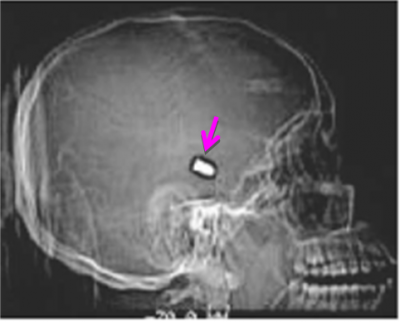

חבלות בקרקפת כוללות המטומות וקרעים. עקב עושר בכלי הדם, קרעים בקרקפת נוטים לדמם מאוד והחולה יכול לאבד דם רב מחבלה שטחית יחסית. הטיפול הראשוני הוא לחץ מקומי כנגד עצם הגולגולת. לחץ מספיק כדי לעצור את הדם. לאחר מכן בחתכים קוויים לאחר הטריה תופרים. חתכים מורכבים דורשים יותר הטריה ולפעמים כיסוי עם מתלי עור של החלק הניזוק. שברים בגולגולות, במיוחד שברי דחיסה (Depressed skull fracture), מסוכנים עקב הלחץ או הפגיעה במעטפות המוח או במוח עצמו (איור 5.16).

האבחנה היא קלינית ורנטגנית. במישוש ניתן להרגיש שקע בגולגולת, וב-CT ניתן לראות את השבר בגולגולת (תצלום 3.16). שברי דחיסה השקועים מעבר ל-5 מ"מ מחייבים התערבות כירורגית להוצאתם. יוצאים מהכלל הם אותם שברי דחיסה שממוקמים מעל הסינוסים של הדורה והרמתם עלולה לגרום לקרע של הסינוס ולדימום שקשה לשלוט עליו. שברים מורכבים עם חשיפה של המוח מחייבים התערבות כירורגית מוקדמת (תוך 12 שעות) למניעת התלקחות זיהומים במקום. עד אז יש לחבוש את המקום באופן סטרילי. אין לנסות להוציא חלקים גרמים או גופים זרים מהפצע או לתפור אותו לפני שהחולה מוכנס לחדר ניתוח, העומד מוכן לביצוע פתיחת גולגולת (Craniotomy) במקרה הצורך.